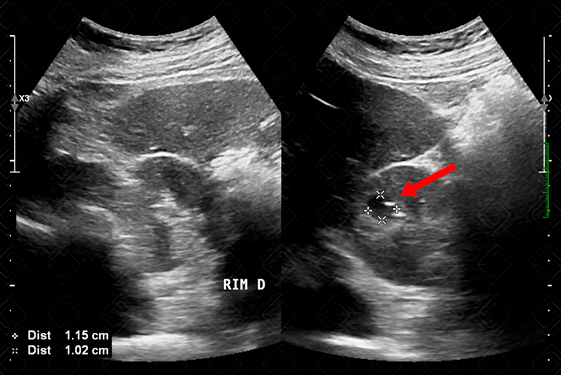

Texto alternativo para a imagem Figura 3. Créditos: Dra. Elazir Mota - Rio de Janeiro/RJ

Descrição da figura 3: Ultrassonografia do abdome total. Imagem anecoica, com discretas calcificações periféricas e sem fluxo ao Doppler colorido, compatível com cisto renal direito (seta vermelha).